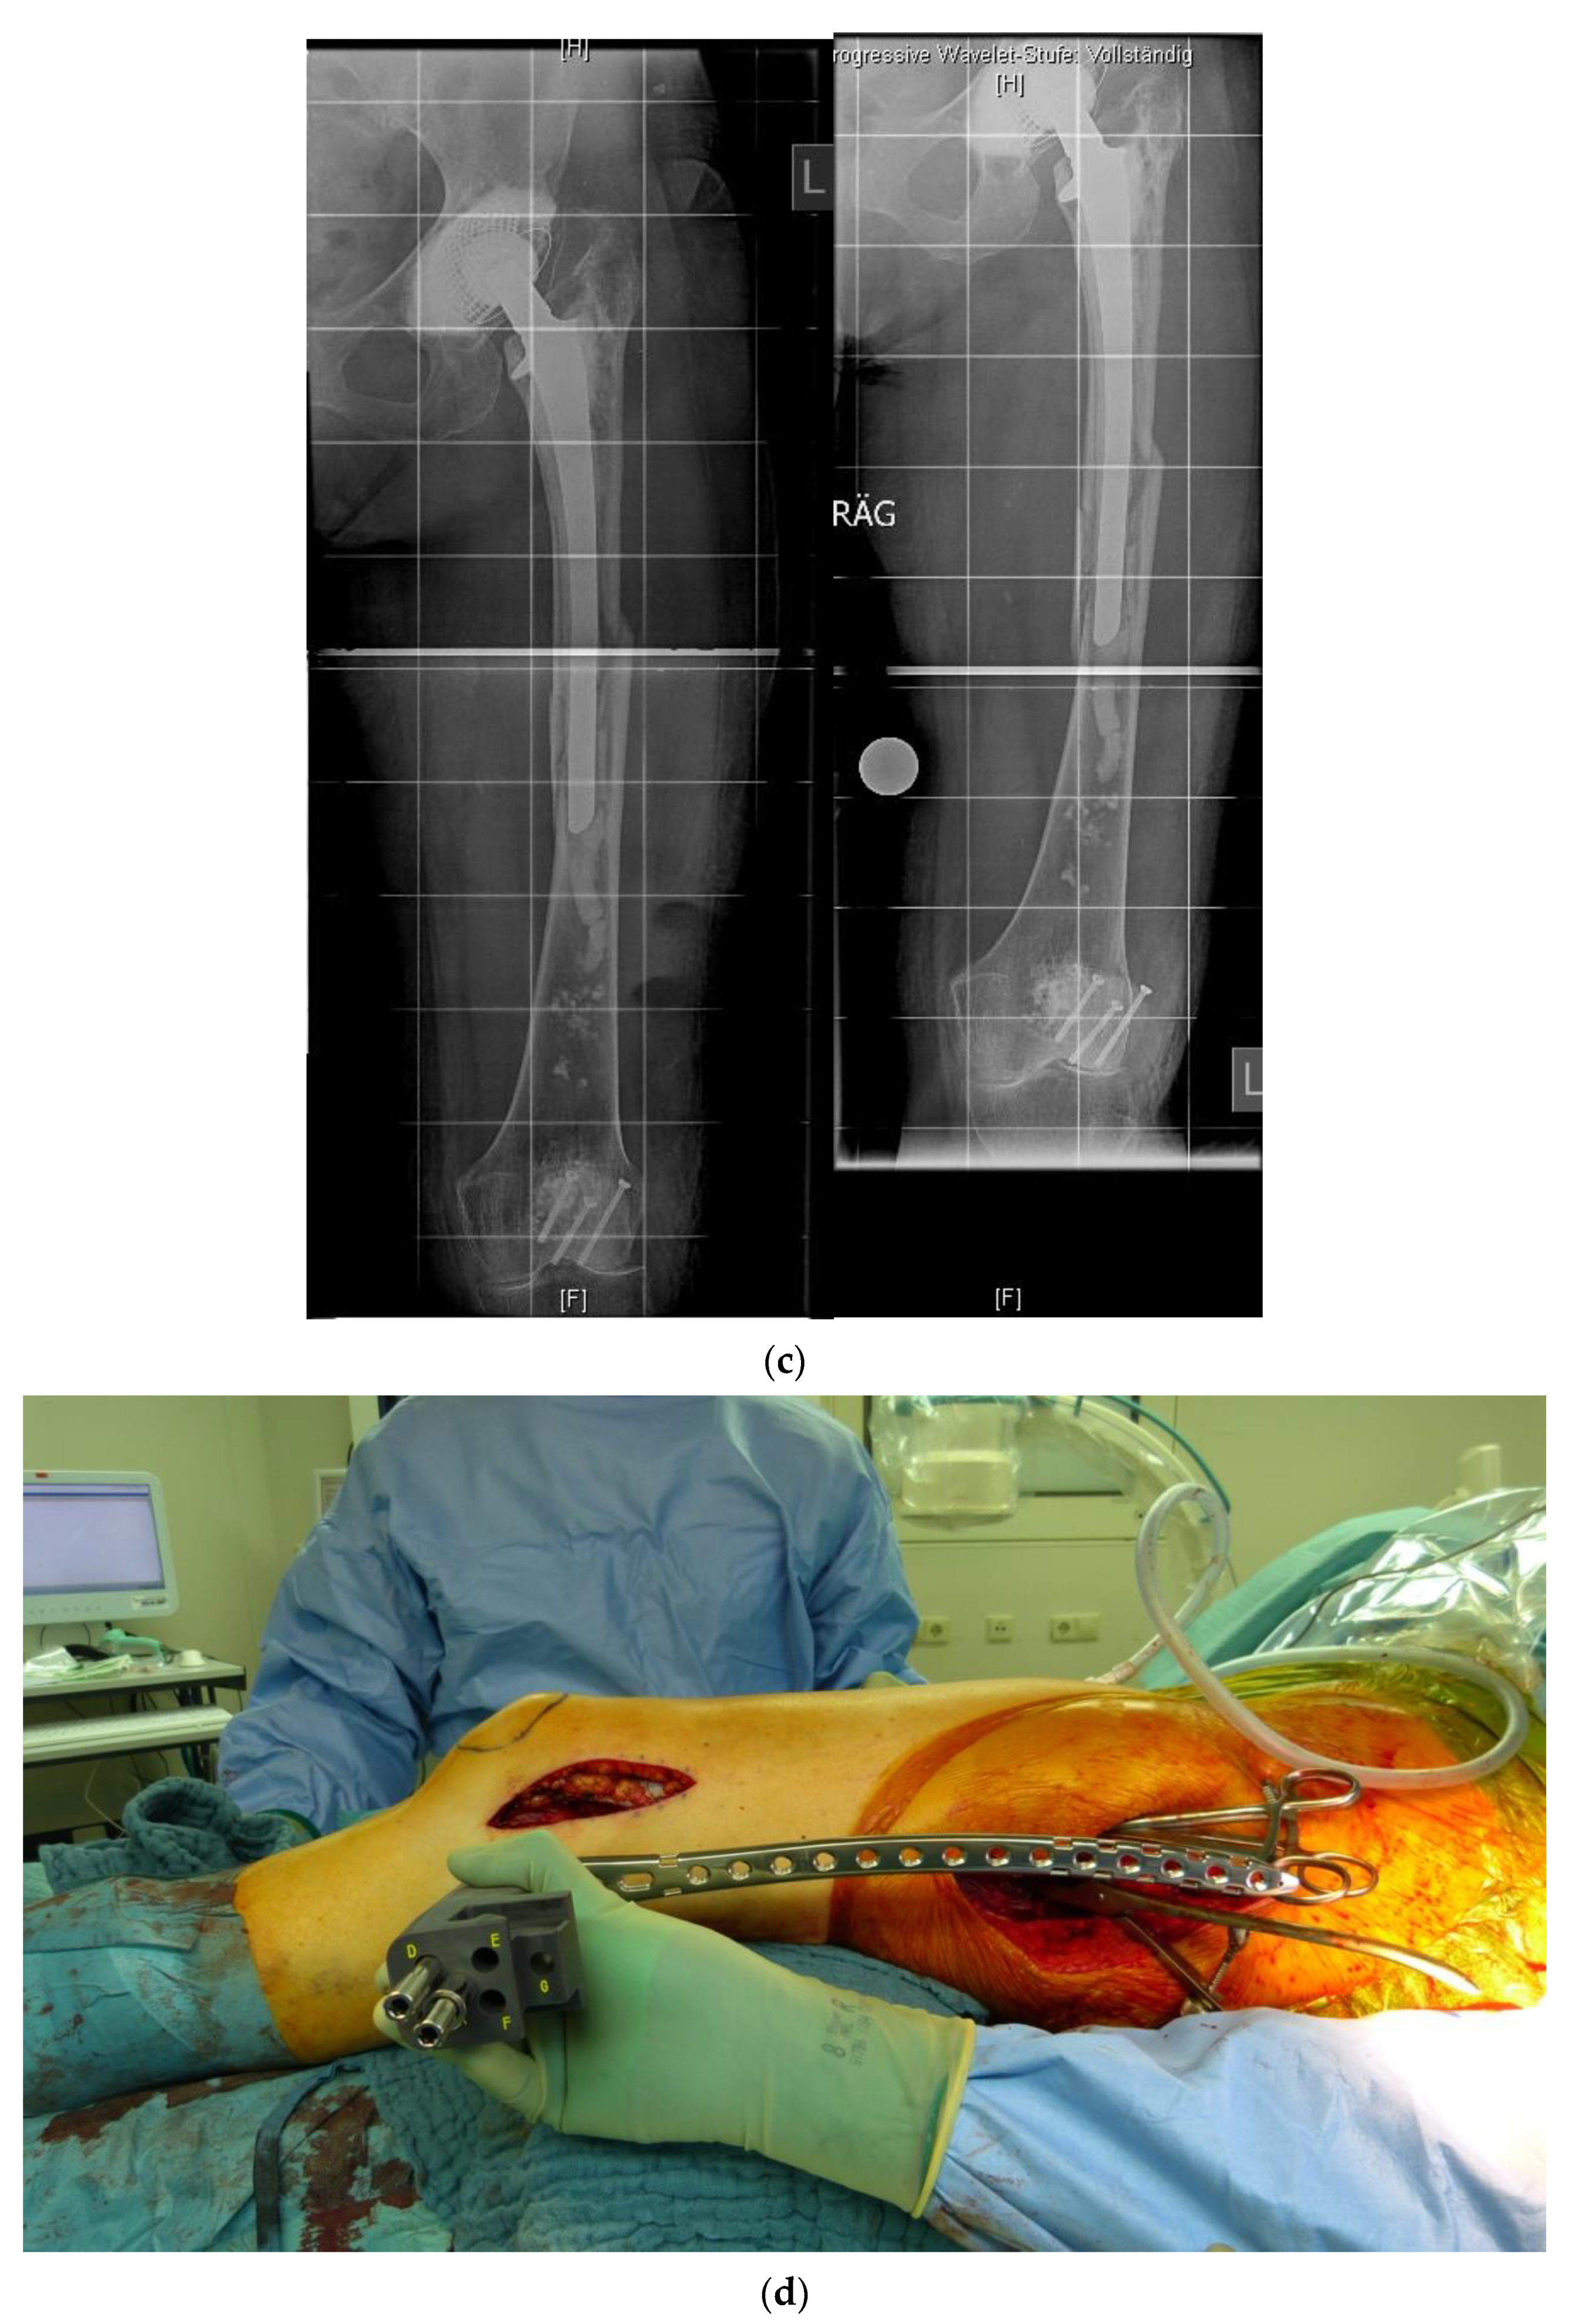

In revision cases and interprosthetic fractures, double plating is an alternative treatment option to avoid high-risk operations such as a total femur replacement. Figure 4 shows a successfully treated hypertrophic non-union after several interprosthetic re-fractures, using double plating in combination with autologous bone-grafting and growth factor application.

Figure 4.

(a) Interprosthetic hypertrophic non-union. Intraoperative situs showing the failed plate fixation and the non-union. (b) Intraoperative situs showing the double plating. (c) Double plating combined with bone-grafting and growth factor application. (d) Postoperative follow-up X-rays after 6 weeks, 12, and 24 months, demonstrating complete healing and remodeling of the fracture.